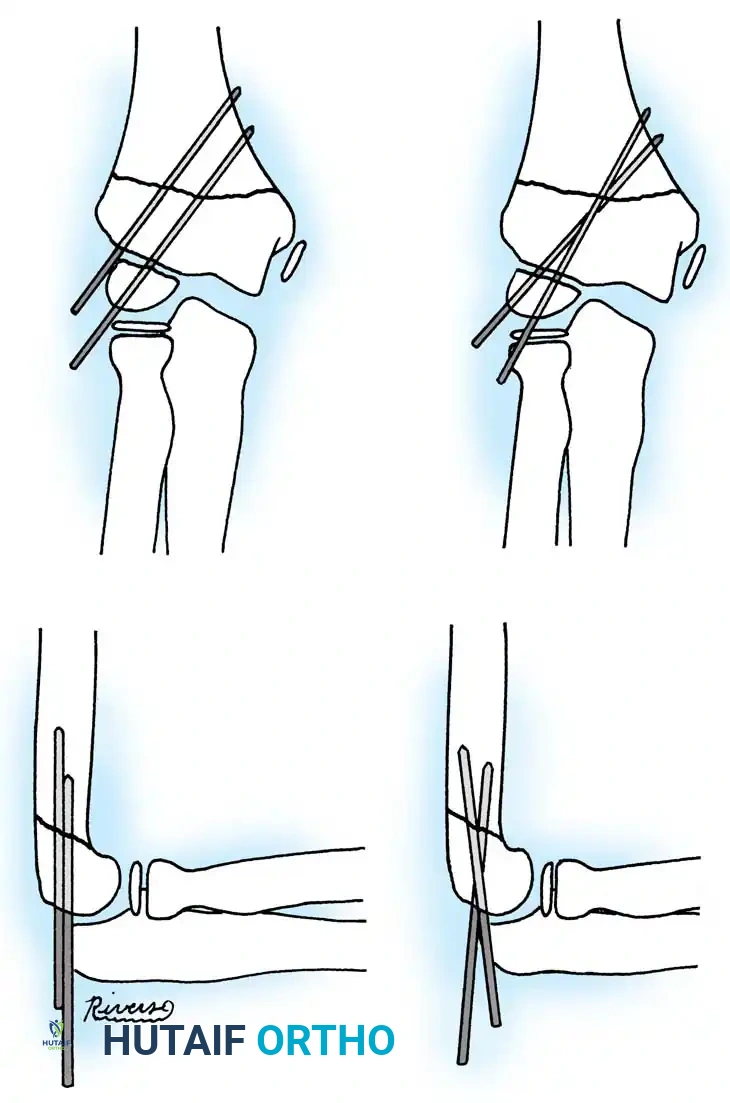

The Metaizeau Technique (Elastic Stable Intramedullary Nailing)

Gonzalez-Herranz et al. and Metaizeau revolutionized the treatment of displaced radial neck fractures (O’Brien types II and III) using retrograde intramedullary pinning. This technique boasts excellent results in over 94% of cases.

- Entry Point: A small incision is made over the distal lateral radial metaphysis, taking care to protect the superficial radial nerve.

- Pin Preparation: A steel Kirschner wire or titanium elastic nail (TEN) is sharply bent at the distal 1.5 cm.

- Insertion: The wire is advanced retrograde through the medullary canal until the bent tip engages the displaced proximal epiphysis.

- Reduction: The pin is rotated 180 degrees around its long axis. The bent tip acts as a cam, elevating the radial head and shifting it medially into anatomical position beneath the lateral condyle.

Fig. 33-44 A-D, Reduction of radial head by leverage method and retrograde intramedullary pinning with Kirschner wire.